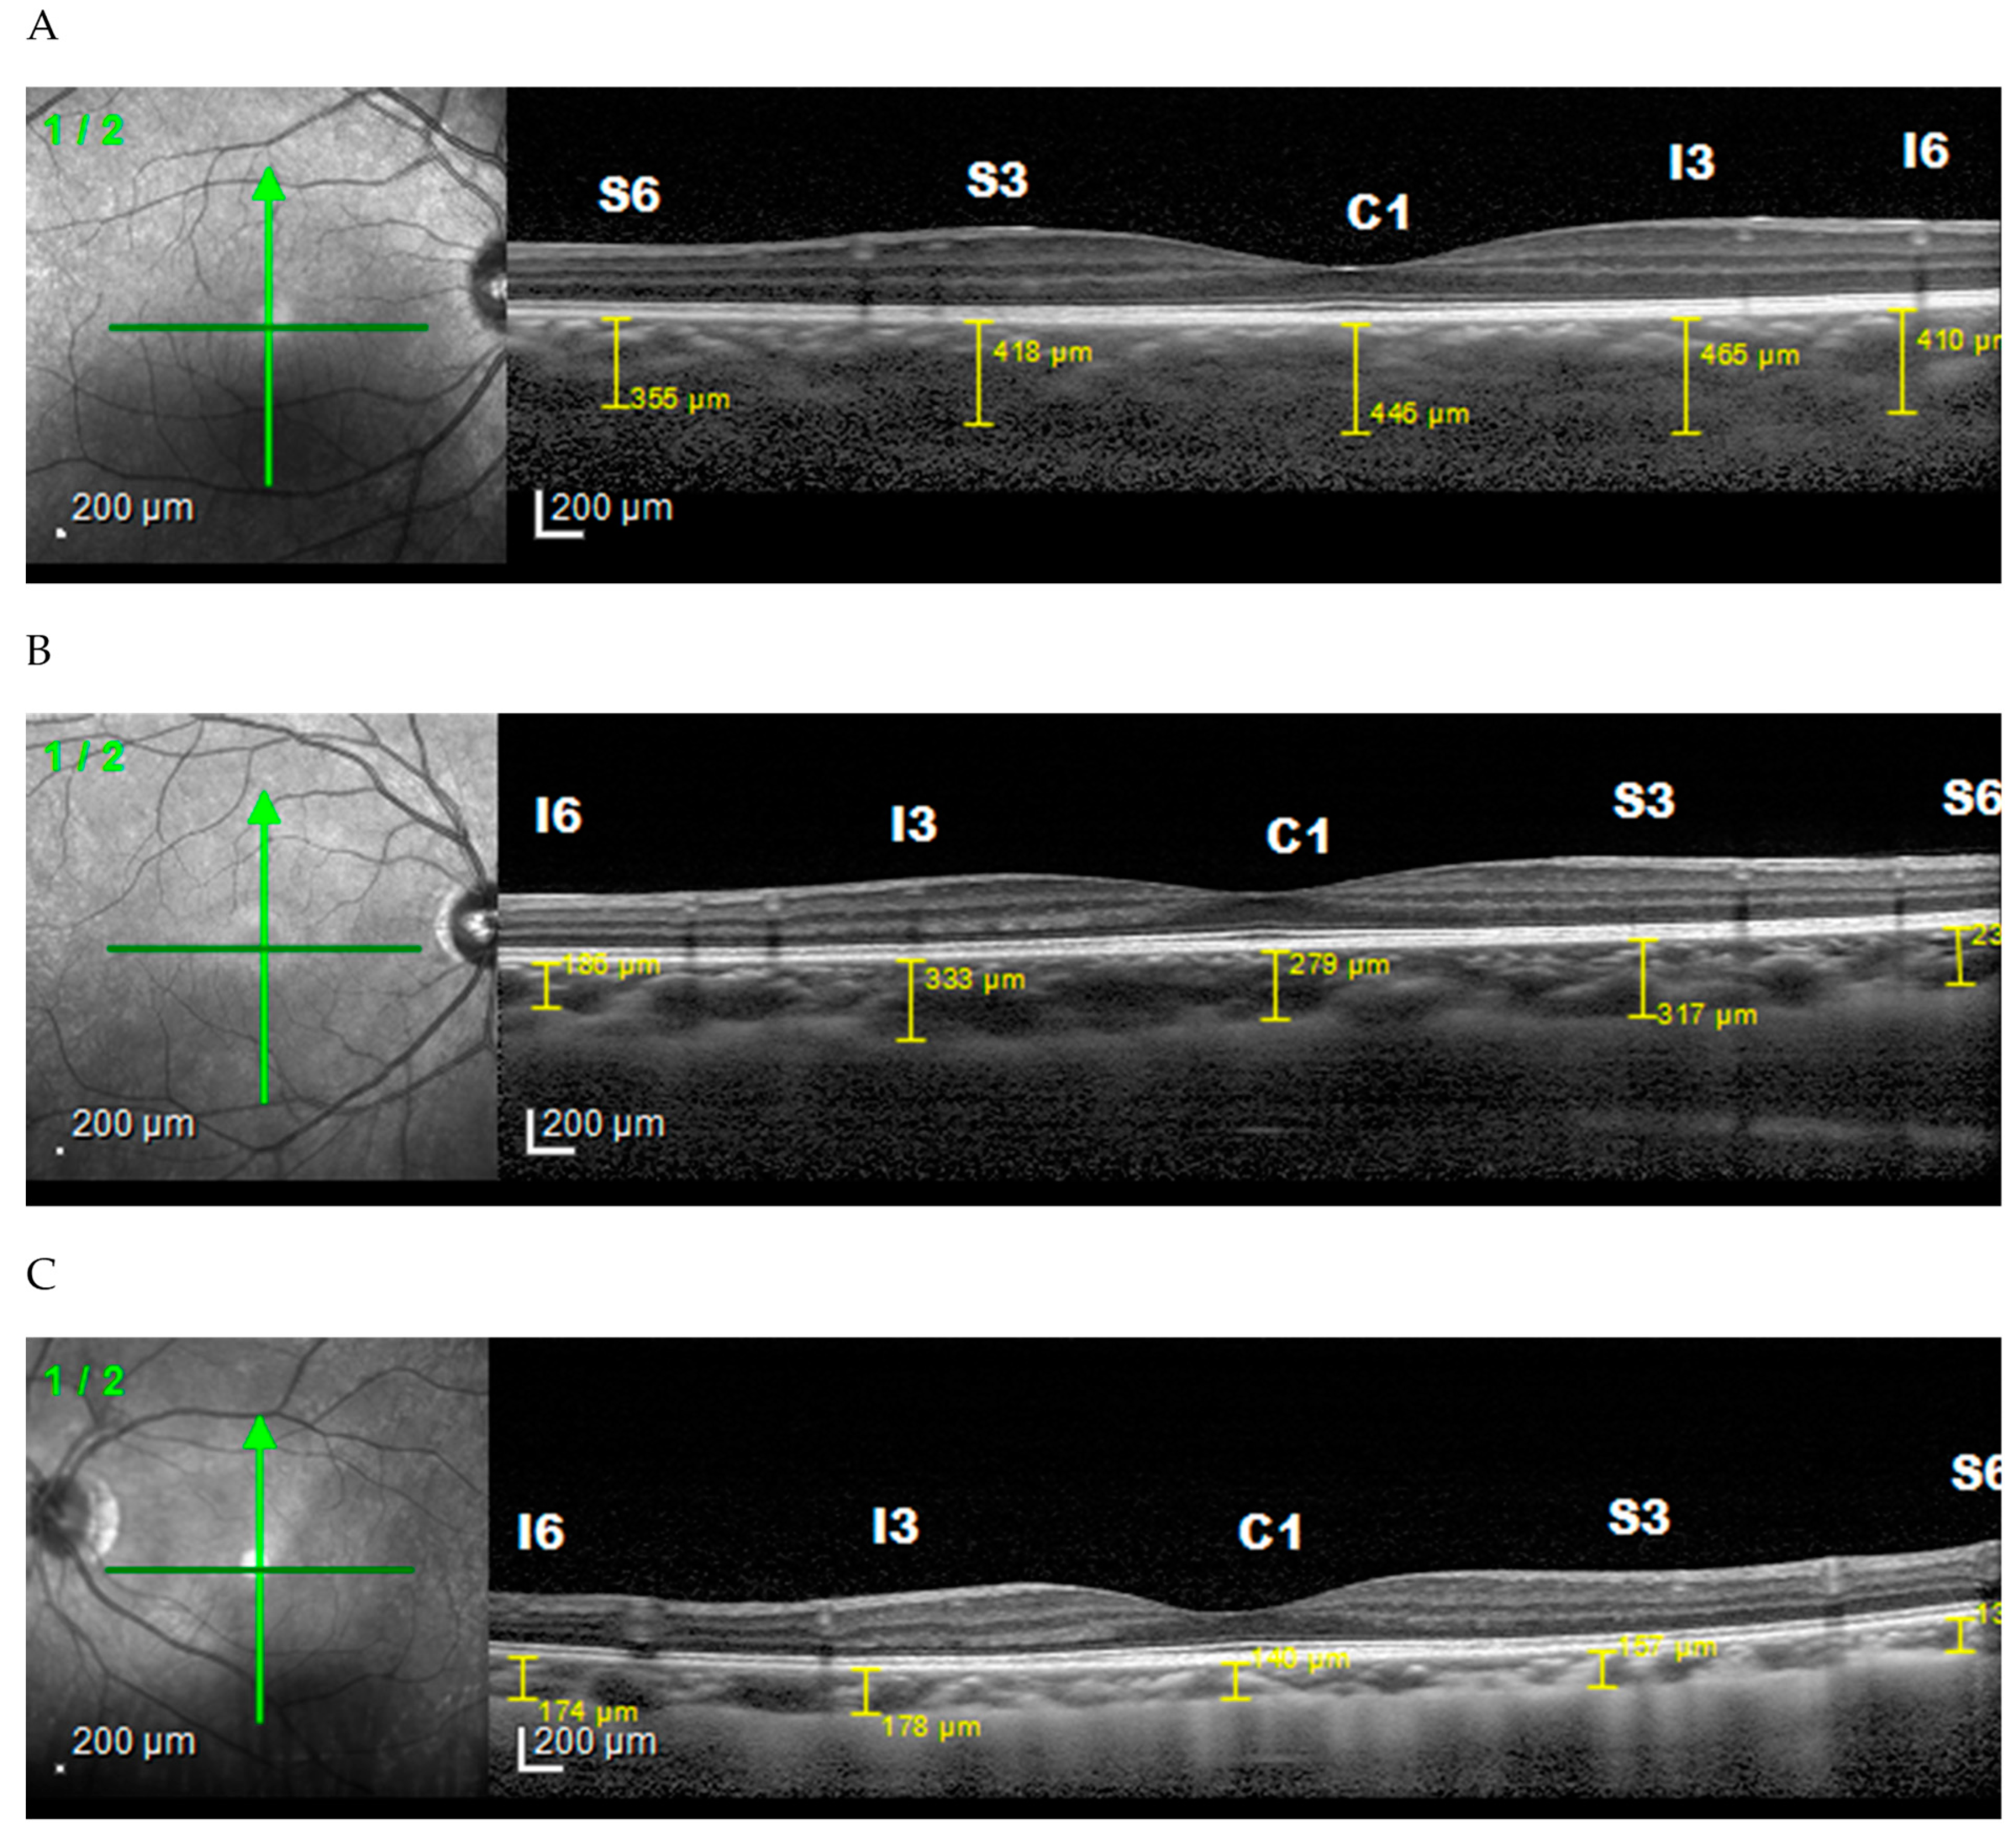

3. Results